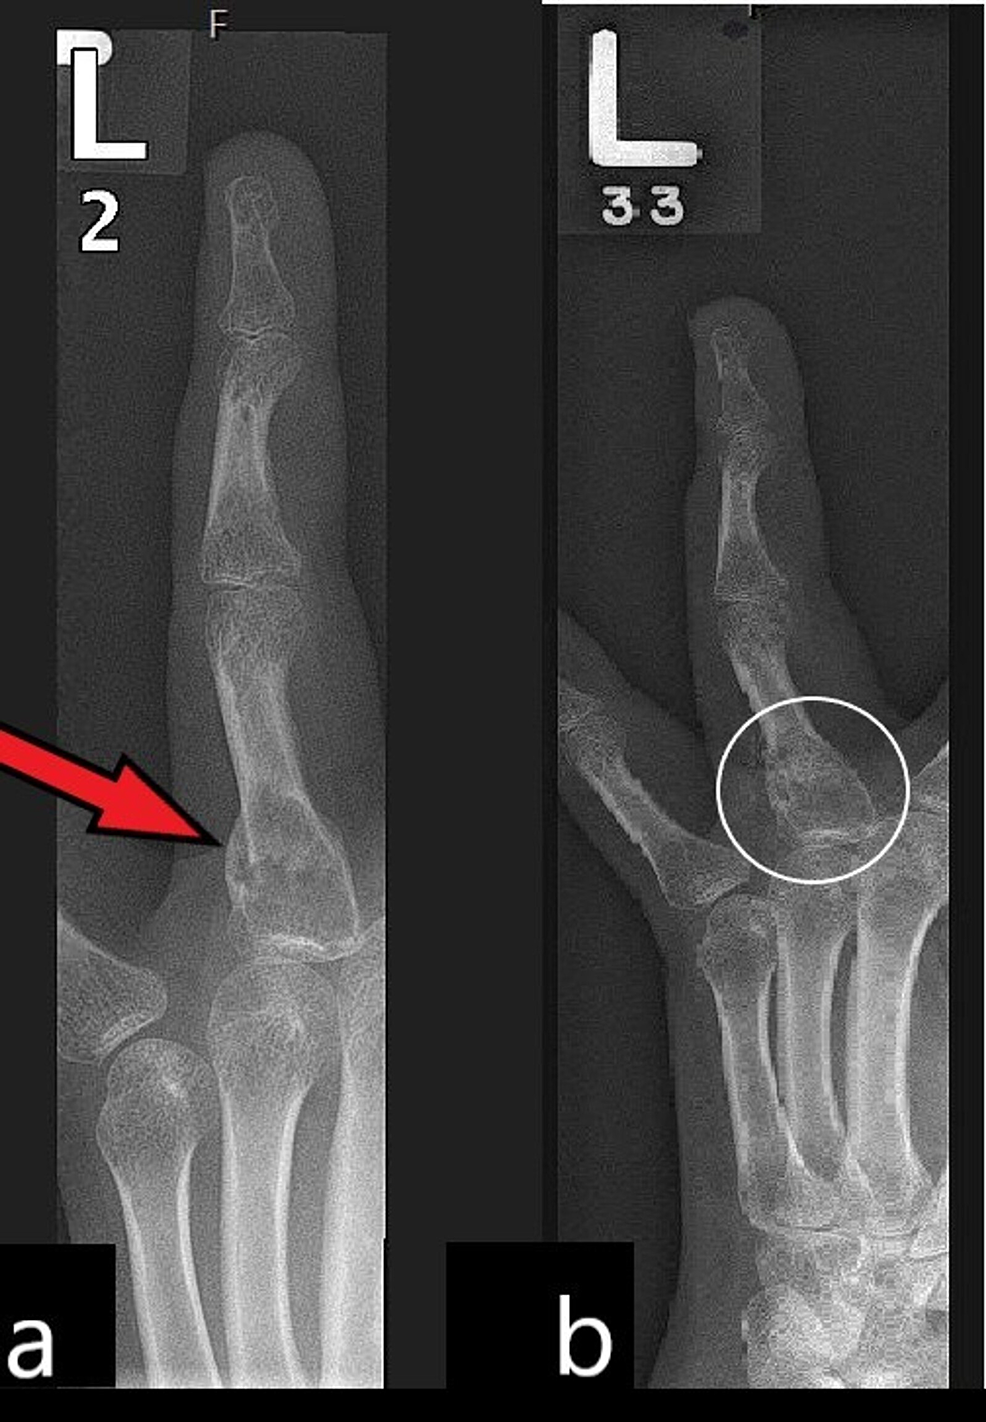

Zimmer Hand Fracture. fractures of the thumb are usually associated with local bruising, swelling, pain and loss of function, with or without deformity. Hand fracture system plates were designed to be modified to meet the needs of the patient and the fracture. Metacarpal and phalangeal fractures are common and constitute a high proportion of all referrals to hand clinics. Hand fracture system plates were designed to be modified to meet the needs of the. to meet the challenge of treating patients with traumatic injuries, zimmer biomet offers a wide range of fracture fixation. Hand fracture system 14 | plate options straight the a.l.p.s. For metacarpal and phalangeal procedures that often involve complex. the a.l.p.s hand fracture system is intended for stabilisation and fixation of small bone fragments in fresh fractures,. zimmer biomet tv provides a comprehensive video catalog of instructional and educational content to support healthcare. low profile, locked plating, anatomically contoured.